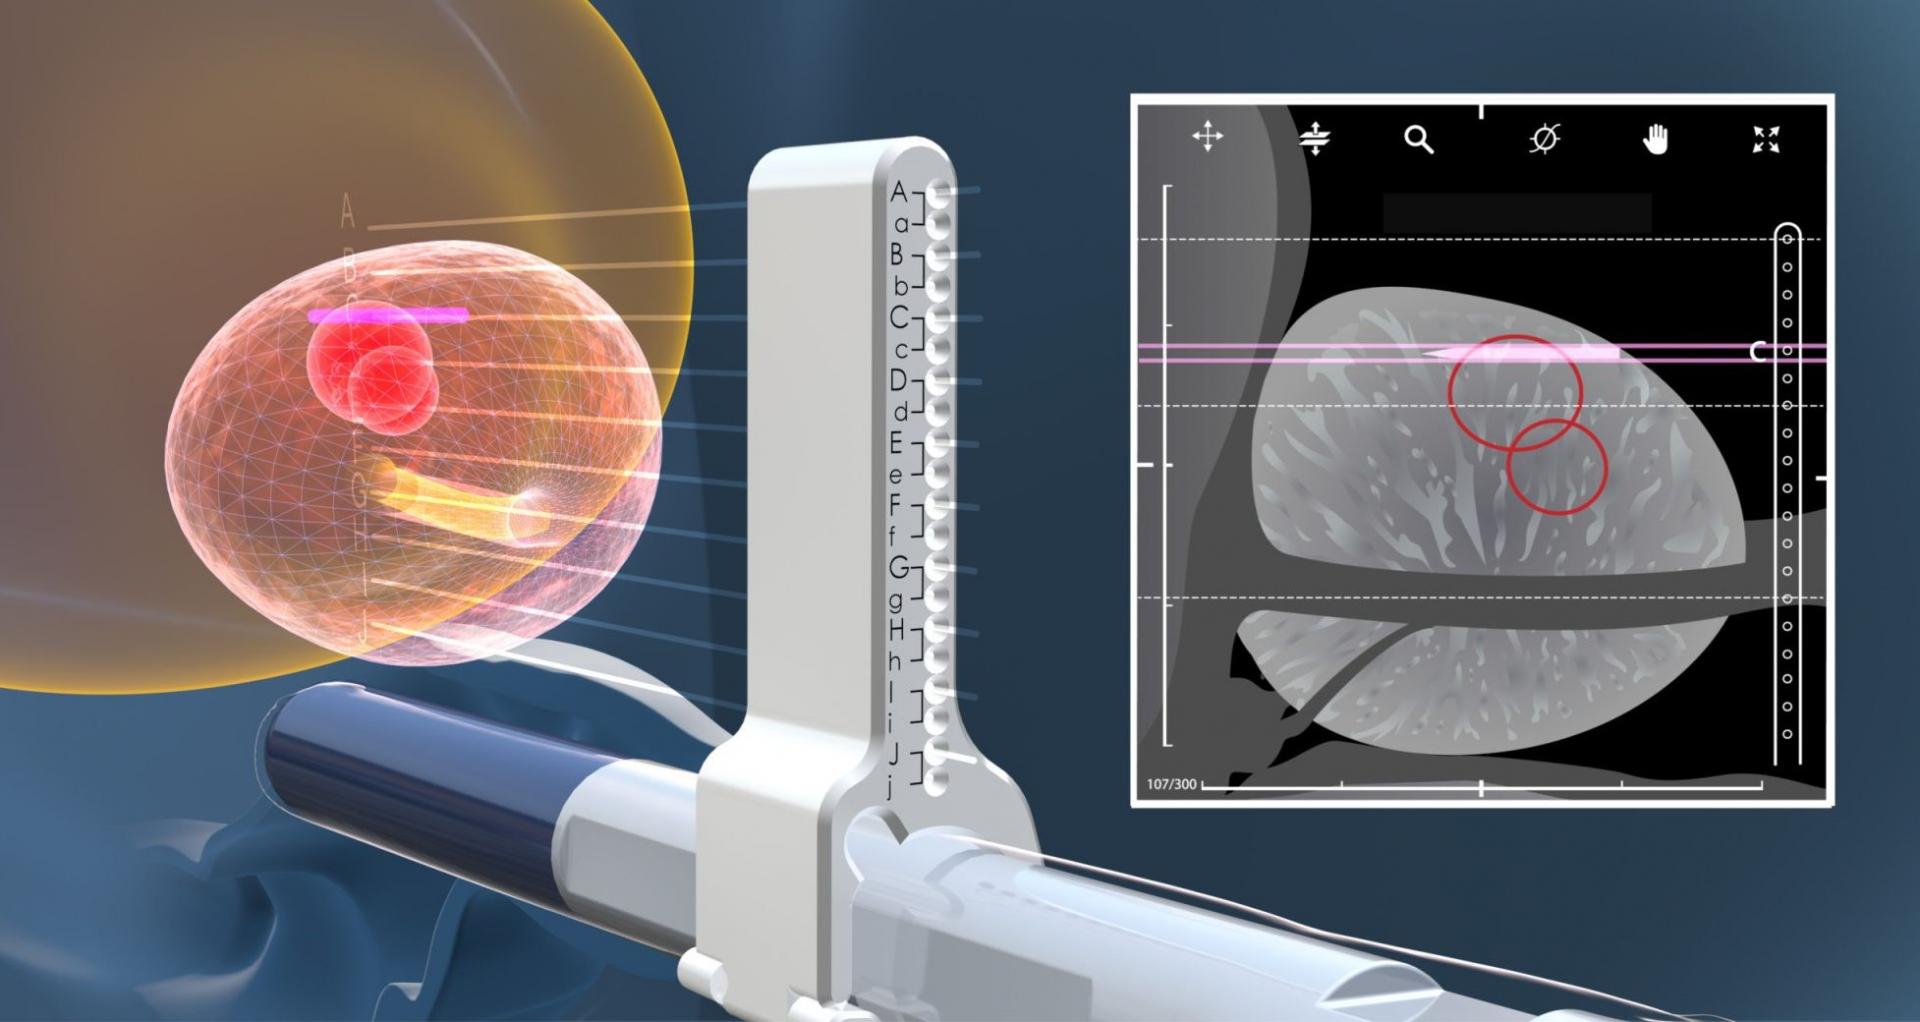

- Modul sinh thiết và điều trị u xơ tiền liệt tuyến (TUR) qua ngả trực tràng dưới dướng dẫn siêu âm _Prostate Imaging & Biopsy: Đặc biệt kỹ thuật điều trị u xơ tiền liệt tuyến bằng hạt phóng xạ (brachytherapy)

- Gá sinh thiết dùng với đầu dò siêu âm các loại